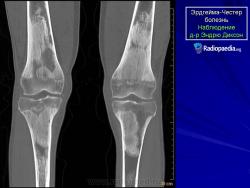

Эрдгейма - Честера болезнь.

Болезнь (или синдром) Эрдгейма-Честера является редким заболеванием. Это гистиоцитоз клеток без островков Лангерганса (небольшие скопления клеток, рассеянные по поджелудочной железе, которые секретируют гормоны инсулин и глюкагон. Существуют три гистологических типа этих клеток: альфа-, бета- и дельта-клетки; они соответственно производят глюкагон, инсулин и соматостатин), затрагивающая лиц среднего возраста, описанная впервые Уильямом Честером и Якобом Эрдгеймом в 1930 году.

Болезнь Эрдгейма-Честера характеризуется ненормальным разростанием лейкоцитов особого типа, гистиоцитов (также называются макрофаги соединительных тканей), что приводит к невозможности фильтрации соединительных тканей, в частности костного мозга трубчатых костей.

Открыть увеличенную версию (194K)